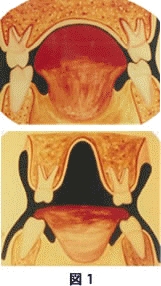

その上アレルギーなどの原因で舌の位置が異常をきたすようになると、下顎の位置は後退し、咽頭部での気道の狭窄が起こり、睡眠障害が起こったり、いびきをかいたりするようになります。

気道の狭窄

このように、鼻気道閉塞による影響でかみ合わせと筋肉のバランスは崩れ、時間をかけて筋肉と顎関節に影響が出てくるのです。鼻気道閉塞の原因はいろいろあります。